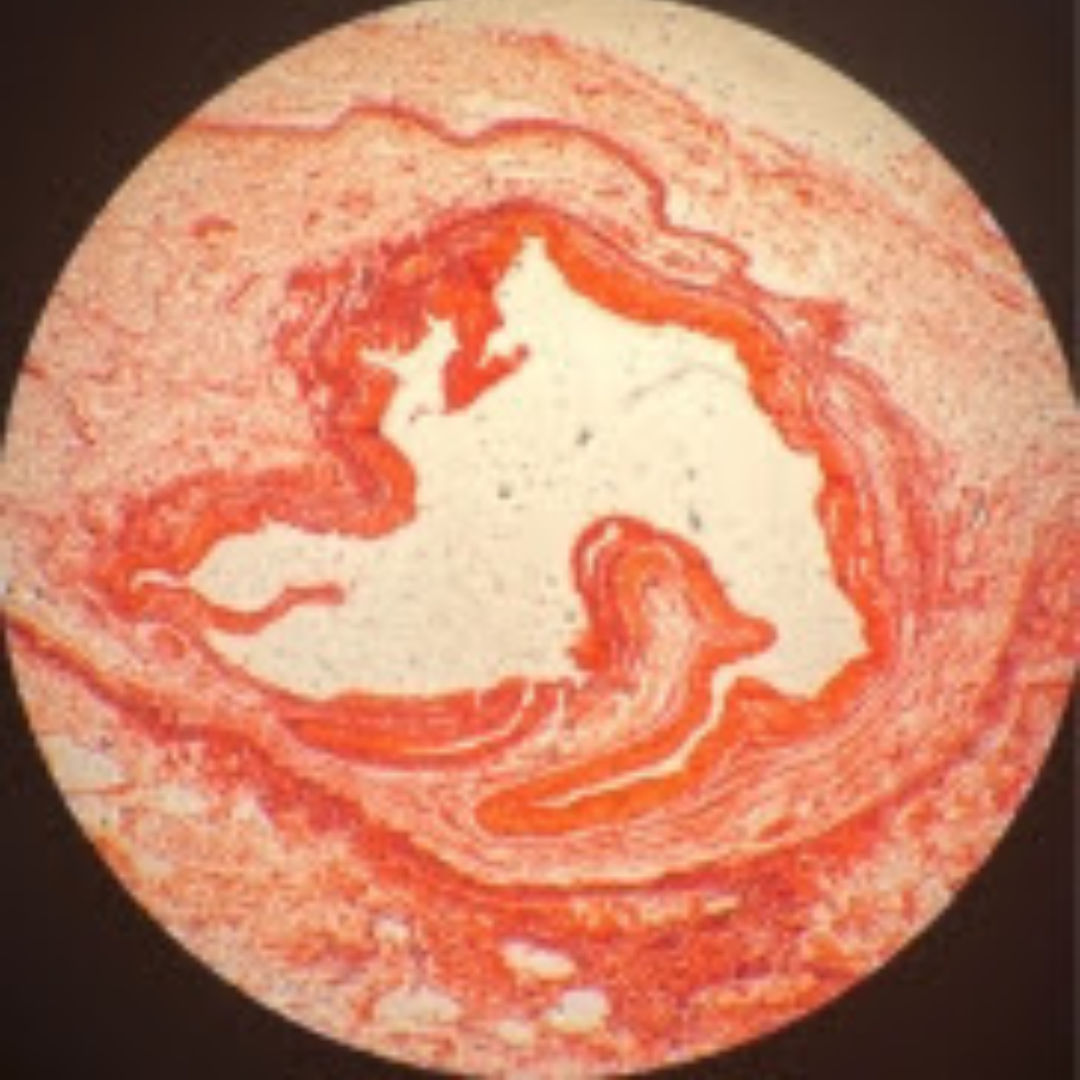

Muscular Arteries (Medium Sized Arteries)

Muscular Arteries (Medium Sized Arteries)

Muscular Arteries (Medium Sized Arteries)